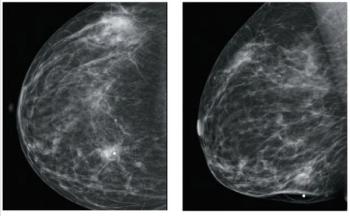

A 46-year-old woman had a routine screening mammogram that showed new calcifications in the posterior left breast. A diagnostic mammogram showed several small punctate calcifications, and a 6-month interval follow-up was recommended.